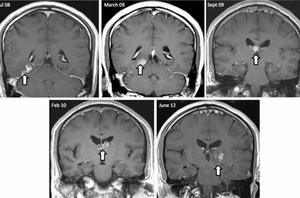

عوارض «وای فای» بر مغز / کرم 40 میلیمتری در مغز یک انگلیسی!

شایعترین علت سکتههای مغزی چیست؟ /تصویری جراحی مغز از راه میانبر توسط ربات